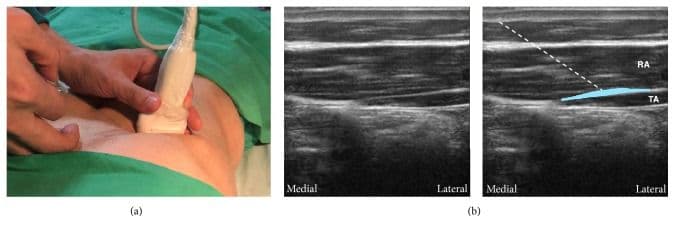

Лінійний датчик розміщують вздовж нижнього краю грудної клітки якомога медіальніше та краніальніше. M. rectus abdomini та його задня сполучнотканинна піхва візуалізуються разом з m. transversus abdominis [5,6,13,25].

Цільовою є фасціальна площина між задньою сполучнотканинною піхвою m. rectus abdominis та m. transversus abdominis. Голку вводять вище прямого м'яза живота близько до середньої лінії та просувають у латеральному напрямку. Ціллю ін'єкції є поширення місцевого анестетика між задньою сполучнотканниною піхвою прямого м'яза живота та переднім краєм поперечного м'яза живота [5,6,13,25].